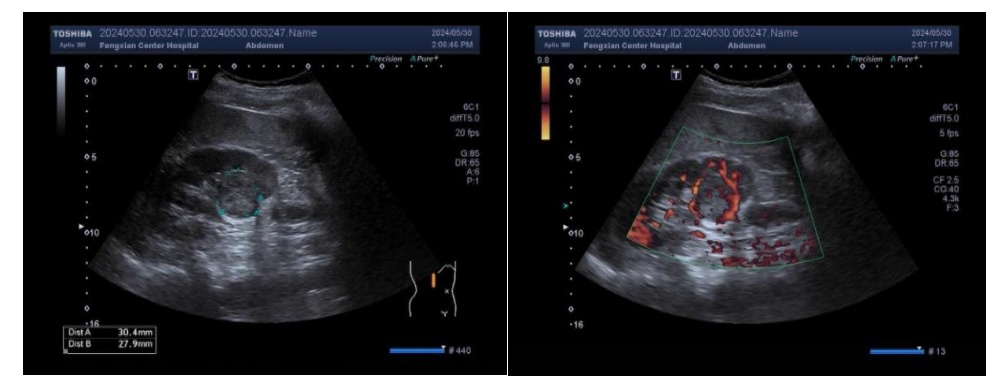

事情还要回溯至半年前。这位老先生姓钱,今年61岁。5月30日,钱先生因右下腹疼痛到区中心医院泌尿外科就诊。超声检查中,王岚发现钱先生的右肾有轻微积水,并在输尿管上端找到了引起尿路梗阻的结石。尽管引起钱先生腹痛的“真凶”已经找到,可“较真”的王岚仍对肾脏仔仔细细地扫查了一遍,意外地在右肾中下部发现了一个与正常肾脏组织极其相似的“可疑”团块。经过反复扫查比对,王岚确信这里藏着一个肿瘤,而且恶性的概率很大!

通常情况下,早期肾透明细胞癌通常因为体积小,肿瘤回声与肾实质极其相似而容易漏诊,经造影检查下的检出率和诊断准确率较高。但王岚凭借其认真仔细的专业态度,敏锐地发现了早期肿瘤,帮助钱先生成功保住了右肾。

定期健康体检。对于可疑肿块进一步检查:超声造影或者CTU、MRI。超声造影可以更清晰显示灰阶超声难以显示或不能明确的小肾癌,透明细胞癌一般高增强快进快退,假包膜的环形增强为特征性表现,不均匀增强,可以更容易发现坏死区,提高诊断准确率。